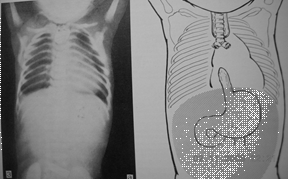

Рис.10. Атрезия пищевода без трахеопищеводного свища (изолированная атрезия), (прямая проекция)

Рис.12. Атрезия пищевода с нижним трахеопищеводным свищем (прямая проекция)